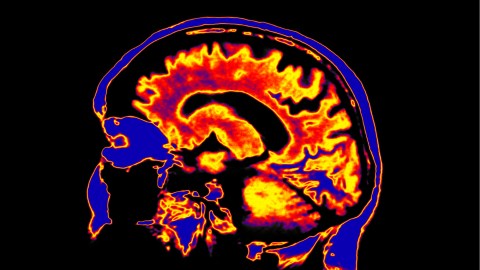

For the truth is that despite the tremendous success of quantum physics, when it comes to its applications—including all of our digital and nuclear technologies—its interpretation remains uncertain, a target of heated debate among physicists. (At least among those who care about deeper foundational questions, certainly not the majority.) As for the workings of the brain, in particular how it engenders our mind and consciousness, we still know precious little—even though advances in imaging techniques have revealed how clusters of neurons, often in different regions of the brain, blink on and off under different stimuli, like lights in a Christmas tree.